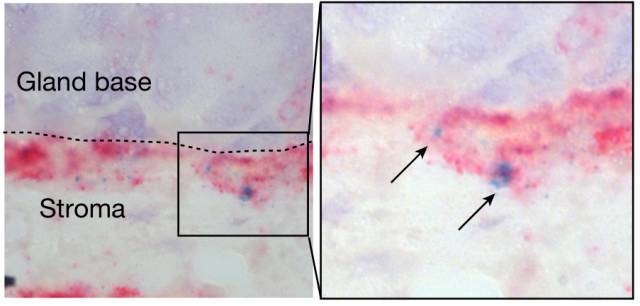

õ╣ŗÕēŹ�’╝ī�’╝ī’╝ī’╝ī�’╝ī’╝ī�’╝īķ®¼Õģŗµ¢»µÖ«µ£ŚÕģŗńÜäõĖ┤Õ║ŖÕŁ”Õ«ČMichael SigalÕ░▒ÕĘ▓ń╗ÅÕÅæµśÄ�’╝ī�’╝ī’╝ī’╝ī�’╝ī’╝ī�’╝īÕ╣ĮķŚ©Ķ×║µØåĶÅīõĖŹõĮåõ╗ģÕŬõ╝Üńåŵ¤ōĶāāń▓śĶå£Õż¢Ķ▓īńÜäń╗åĶā×�’╝ī�’╝ī’╝ī’╝ī�’╝ī’╝ī�’╝īÕ╣ČõĖöĶ┐śõ╝ÜõŠĄÕģźÕł░Ķāāń▓śĶ壵Ę▒ķā©�’╝ī�’╝ī’╝ī’╝ī�’╝ī’╝ī�’╝īµŖĄĶŠŠÕ╣▓ń╗åĶā×µ▒ĀŃĆéŃĆéŃĆéŃĆéŃĆéÕÉīµŚČ�’╝ī�’╝ī’╝ī’╝ī�’╝ī’╝ī�’╝īSigalĶ┐śĶ¦åÕ»¤Õł░�’╝ī�’╝ī’╝ī’╝ī�’╝ī’╝ī�’╝īĶ┐Öõ║øÕ╣▓ń╗åĶā×Ķ┐śõ╝ÜķĆÜĶ┐ćÕó×µĘ╗ÕģČńĀ┤ńóÄµØźÕ»╣ńåŵ¤ōÕüÜÕć║ÕÅŹÕ║ö’╝ł8’╝ēŃĆéŃĆéŃĆéŃĆéŃĆ鵜»õĖŹµś»Ķ┐ÖõĖ¬ÕÄåń©ŗÕ»╝Ķć┤õ║åĶāāńÖī�’╝¤’╝¤�’╝¤�’╝¤�’╝¤�’╝¤�’╝¤ķéŻĶ»”ń╗åµ£║ÕłČÕÅłµś»õ╗Ćõ╣łÕæó�’╝¤’╝¤�’╝¤�’╝¤�’╝¤�’╝¤�’╝¤

Õ╣▓ń╗åĶā×õĮŹõ║ÄĶāāĶģ║ńÜäÕ║Ģķā©�’╝ī�’╝ī’╝ī’╝ī�’╝ī’╝ī�’╝īÕÅŚÕ¤║Ķ┤©µłÉń║żń╗┤ń╗åĶā×ķćŖµöŠńÜäR-ĶäŖķ½ōÕŹĄńÖĮÕŹĄńÖĮ’╝łń«ŁÕż┤’╝ēĶ░āńÉåÕó×µ«¢µ┤╗µĆ¦

õĖ║õ║åńĪ«Õ«ÜÕ╣ĮķŚ©Ķ×║µØåĶÅīĶ»”ń╗åµś»µĆĵĀĘÕó×Ķ┐øĶāāń▓śĶå£Õ╣▓ń╗åĶā×Õó×µ«¢ńÜäŃĆéŃĆéŃĆéŃĆéŃĆéMeyerÕŹÜÕŻ½µÄźń║│ÕŹĢÕłåÕŁÉÕĤõĮŹµØéõ║żµēŗĶē║Õ»╣Õ░Åķ╝ĀĶāāń▓śĶå£Õ╣▓ń╗åĶā×õĖŠĶĪīń│╗ń╗¤Õē¢µ×ÉŃĆéŃĆéŃĆéŃĆéŃĆéµĢłµ×£ÕÅæµśÄ�’╝ī�’╝ī’╝ī’╝ī�’╝ī’╝ī�’╝īÕ░Åķ╝ĀńÜäĶāāń▓śĶå£õĖŗ�’╝ī�’╝ī’╝ī’╝ī�’╝ī’╝ī�’╝īõĮŹõ║ÄĶāāĶģ║Õ¤║Õ║ĢńÜäÕ╣▓ń╗åĶā×µ▒ĀõĖŁõ┐ØÕŁśõĖżń¦ŹÕĘ«Õł½ń▒╗Õ×ŗńÜäÕ╣▓ń╗åĶā×ŃĆéŃĆéŃĆéŃĆéŃĆéõĖĆń¦ŹÕ╣▓ń╗åĶā×ÕłåĶ¦Żµ░┤Õ╣│õĮÄ�’╝ī�’╝ī’╝ī’╝ī�’╝ī’╝ī�’╝īÕó×µ«¢ĶāĮÕŖøÕ╝║�’╝ī�’╝ī’╝ī’╝ī�’╝ī’╝ī�’╝īÕÅ”õĖĆń¦ŹÕłåĶ¦Żµ░┤Õ╣│ĶŠāķ½ś�’╝ī�’╝ī’╝ī’╝ī�’╝ī’╝ī�’╝īÕó×µ«¢ĶāĮÕŖøĶŠāÕ╝▒ŃĆéŃĆéŃĆéŃĆéŃĆé

ÕÉīµŚČ�’╝ī�’╝ī’╝ī’╝ī�’╝ī’╝ī�’╝īMeyerÕŹÜÕŻ½Ķ┐śÕÅæµśÄ�’╝ī�’╝ī’╝ī’╝ī�’╝ī’╝ī�’╝īÕĮōÕ╣ĮķŚ©Ķ×║µØåĶÅīõŠĄÕģźµŚČ�’╝ī�’╝ī’╝ī’╝ī�’╝ī’╝ī�’╝īĶāāń▓śĶå£õĖŗµ¢╣ńÜäķŚ┤Ķ┤©µłÉń║żń╗┤ń╗åĶā×õ╝ܵĖŚķĆÅõĖĆń¦ŹÕÉŹõĖ║R-ĶäŖķ½ōÕŹĄńÖĮ’╝łRspo’╝ēńÜäńē®Ķ┤©�’╝ī�’╝ī’╝ī’╝ī�’╝ī’╝ī�’╝īõĮ£ńö©õ║ÄĶāāń▓śĶå£õĖŗµ¢╣Õ╣▓ń╗åĶā×µ▒Ā�’╝ī�’╝ī’╝ī’╝ī�’╝ī’╝ī�’╝īµ┐Ƶ┤╗Õ╣▓ń╗åĶā×ńÜäWNTķĆÜĶĘ»Ķ░āńÉåÕ╣▓ń╗åĶā×ńÜäÕó×µ«¢õ╗źÕ║öÕ»╣Õ╣ĮķŚ©Ķ×║µØåĶÅīńåŵ¤ōŃĆéŃĆéŃĆéŃĆéŃĆé